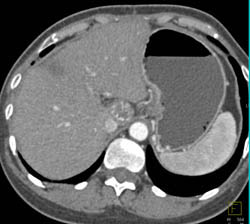

Hepatoma Extends Into the IVC